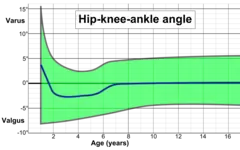

The degree of varus or valgus deformity can be quantified by the hip-knee-ankle angle,[33] which is an angle between the femoral mechanical axis and the center of the ankle joint.[34] It is normally between 1.0° and 1.5° of varus in adults.[35] Normal ranges are different in children.[36]

Hip-knee-ankle angle by age, with 95% prediction interval.[36]

Hip-knee-ankle angle by age, with 95% prediction interval.[36]